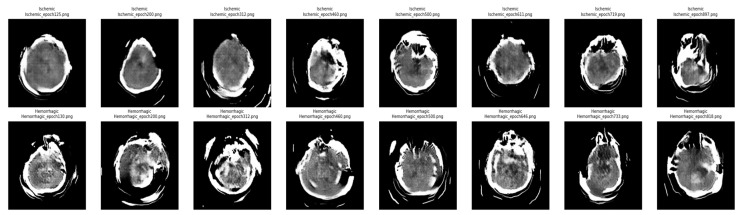

背景与目的:中风仍然是世界范围内死亡和长期残疾的主要原因,需要快速准确的诊断来改善患者的预后。计算机断层扫描(CT)由于其速度、可用性和成本效益而广泛应用于紧急情况。本研究提出了一种基于人工智能(AI)的框架,用于使用土耳其共和国卫生部的CT扫描图像进行多类别中风分类(缺血性、出血性和无卒中)。方法:采用基于视觉变压器(Vision Transformer, ViT)的MaxViT架构作为脑卒中分类的主要深度学习模型。其他变压器变体,包括Vision transformer (ViT)、transformer -in- transformer (TNT)和ConvNeXt,被评估以进行比较。为了提高模型泛化和处理类不平衡,采用了经典的数据增强技术。此外,可解释的人工智能(XAI)使用Grad-CAM++集成,为模型决策提供可视化见解。结果:增强后的MaxViT模型获得了最高的性能,达到了98.00%的准确率和f1评分,优于基线Vision Transformer和其他评估模型。Grad-CAM++可视化证实,所提出的框架有效地识别卒中相关区域,提高透明度和临床信任。结论:本研究有助于开发一种值得信赖的人工智能辅助脑卒中诊断工具,促进其与临床实践的结合,提高急诊科对脑卒中及时和最佳诊断的可及性。

Background & Objective: Stroke remains a leading cause of mortality and long-term disability worldwide, demanding rapid and accurate diagnosis to improve patient outcomes. Computed tomography (CT) scans are widely used in emergency settings due to their speed, availability, and cost-effectiveness. This study proposes an artificial intelligence (AI)-based framework for multiclass stroke classification (ischemic, hemorrhagic, and no stroke) using CT scan images from the Ministry of Health of the Republic of Turkey. Methods: We adopted MaxViT, a state-of-the-art Vision Transformer (ViT)-based architecture, as the primary deep learning model for stroke classification. Additional transformer variants, including Vision Transformer (ViT), Transformer-in-Transformer (TNT), and ConvNeXt, were evaluated for comparison. To improve model generalization and handle class imbalance, classical data augmentation techniques were applied. Furthermore, explainable AI (XAI) was integrated using Grad-CAM++ to provide visual insights into model decisions. Results: The MaxViT model with augmentation achieved the highest performance, reaching an accuracy and F1-score of 98.00%, outperforming the baseline Vision Transformer and other evaluated models. Grad-CAM++ visualizations confirmed that the proposed framework effectively identified stroke-related regions, enhancing transparency and clinical trust. Conclusions: This research contributes to the development of a trustworthy AI-assisted diagnostic tool for stroke, facilitating its integration into clinical practice and improving access to timely and optimal stroke diagnosis in emergency departments.